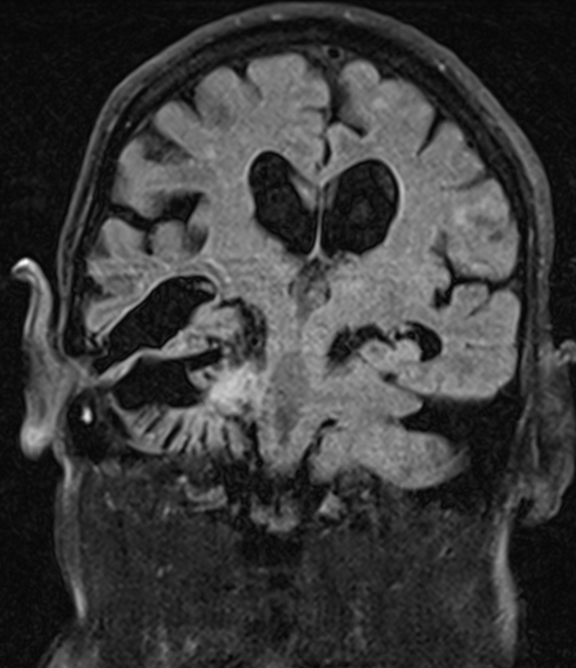

A 79-year-old diabetic male was presented to the emergency department with a one day history of a mild frontal headache and watery discharge from his right ear. His past medical history included previous mastoid surgery, performed more than 50 years ago. The procedure was complicated by postoperative intracranial abscess formation which required neurosurgical intervention and unfortunately resulted in loss of right sided visual acuity. Regrettably, the patient did not attend for continued follow-up and the last contact with the Otolaryngology service had been more than 25 years ago. Examination revealed clear pulsatile otorrhea from the right ear and a sample sent for Beta 2 transferrin testing confirmed the presence of a cerebrospinal fluid (CSF) leak. Microscopic examination of the external auditory canal demonstrated an inflamed external auditory canal with a significant amount of keratin debris, consistent with likely recurrent cholesteatoma, visible beyond a narrow isthmus. A contrast computed tomography (CT) scan was requested emergently and demonstrated a significant amount of intra-ventricular free air (Figure 1) as well as the previous posterior craniotomy defect (arrow). High resolution images of the temporal bone confirmed extensive soft tissue opacification of the middle ear cavity and a defect in the tegmen tympani.

Figure 1: Computed tomography brain, pneumocephalus (Stars), right posterior craniotomy defect (arrow).